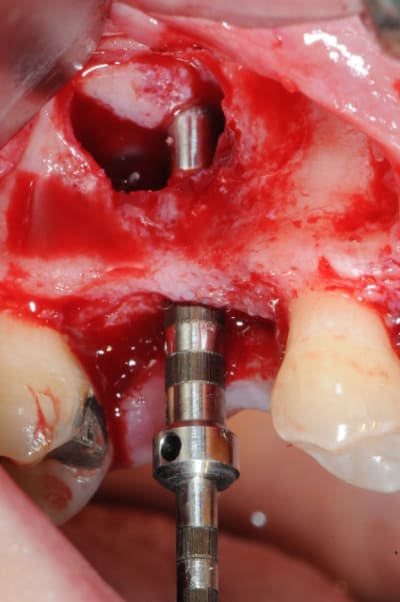

je sais pas si c'est un produit miracle, mais pour les sinus lift, c'est fantastique.

outre le fait de stabiliser un implant dans un sinus type SA4, pas de risque de voir partir le produit comme avec les granules de bioos et autres..

l'application type du VitalOs, avec le bone splitting.

le protocole tel qu'il est d'écrit voudrait que l'on applique d'abord une couche de vital os en palatin - laisser durcir - mettre l'implant puis mettre une dernière couche.

ici, j'ai mis l'implant- maintenu la membrane de Schneider en poussant avec l'embout sur celle ci et terminer l'injection du produit. c'est l'un des avantages de ce produit, il est livré avec deux embouts donc les deux solutions sont possibles pour une même seringue.

Crois-tu qu'on aurait pu tenter du "un temps "dans ce cas précis? la stabilité primaire était-elle suffisante ou as-tu voulu jouer la sécurité en choisissant le 2 temps?